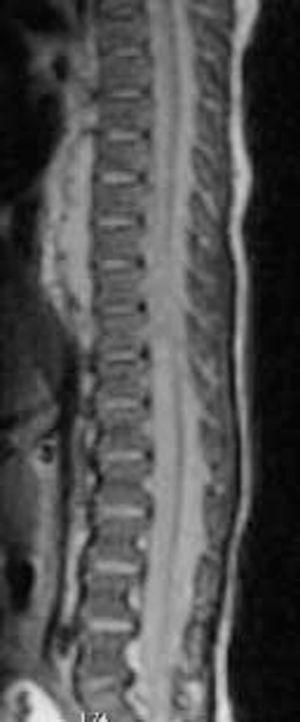

Figura 1. Imágenes del absceso prevertebral de 4 cm de longitud y del empiema epidural obtenidos mediante RM.

Presentamos un caso clínico de empiema epidural en un lactante varón de un mes de edad, que fue intervenido la semana previa al desarrollo del cuadro clínico de estenosis hipertrófica de píloro mediante laparoscopia con acceso umbilical. El paciente desarrolló a los 7 días de la intervención fiebre (máxima 38,8 °C), malestar general y dificultad en las tomas, sin afectación de los signos vitales. En la exploración física inicial no se apreció rigidez de nuca ni déficit neurológico. El hemograma practicado reveló inicialmente 14.100 leucocitos/μl (66,8 % segmentados; 19 % linfocitos), una proteína C reactiva (PCR) > 12 mg/dl y se recogió un hemocultivo. Se realizó una ecografía abdominal para descartar la presencia de una complicación postoperatoria que fue normal, y se inició tratamiento empírico con amoxicilina y ácido clavulánico. Dada la persistencia de la fiebre durante más de 24 h, se decidió repetir la analítica, presentando en el hemograma 24.400 leucocitos/μl (48 % segmentados; 16 % cayados; 2 % metamielocitos; 30 % linfocitos) y una PCR de 38,79 mg/dl. Se realizó una punción lumbar para descartar la presencia de meningitis, obteniéndose pus espeso, motivo por el que el paciente ingresó en la UCI. Finalmente en los cultivos recogidos (sangre y LCR) se obtuvo la presencia de Staphylococcus aureus sensible a oxacilina, por lo que se cambió el tratamiento a cloxacilina y rifampicina. Se practicó una radiografía de tórax (normal), una ecocardiografía (normal) y se realizó un examen neurológico completo que resultó ser normal. Se realizó una ecografía del SNC, donde se apreció la presencia de hiperecogenicidad del espacio extraaxial en la práctica totalidad del raquis, alcanzando un grosor máximo de 5 mm en el espacio L1-L2. Se realizó una RM que demostró la presencia de un empiema epidural (fig. 1), un absceso pulmonar de 2 x 2 cm y un absceso prevertebral de 4 cm. Se repitió la ecografía a las 48 h del tratamiento y se observó una clara disminución de la colección epidural. El tratamiento se mantuvo durante 3 semanas y posteriormente se continuó con cloxacilina únicamente durante 5 semanas más. Dado el antecedente de la intervención quirúrgica y sobre todo, la vía de acceso umbilical empleada, se cree que el origen del empiema epidural haya sido una diseminación del germen favorecida por la vía de acceso de la cirugía.